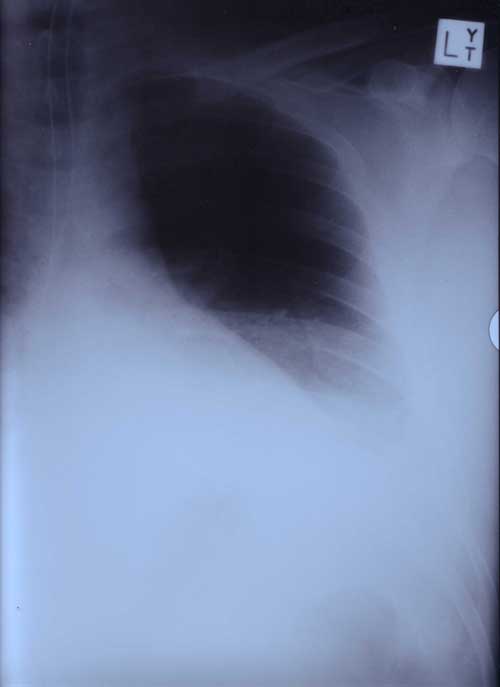

X Rays

22nd January 2000